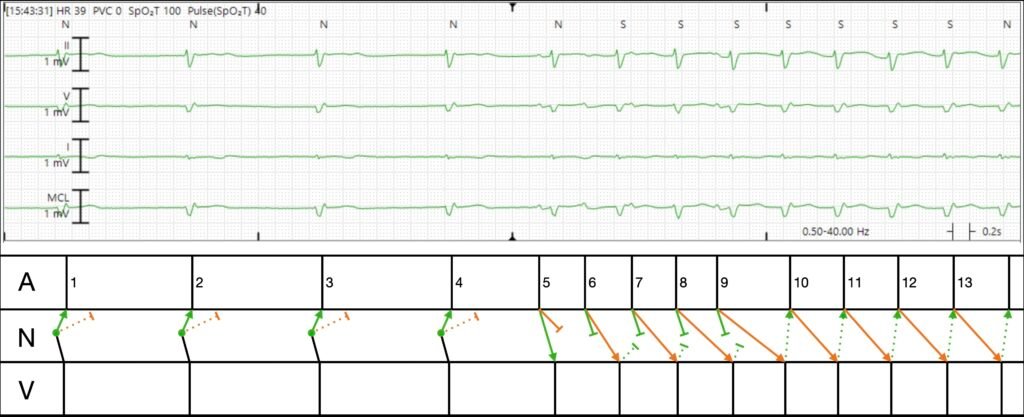

Here is my interpretation with a ladder diagram. Please note that this is just one educated guess. There are other possible reasonable interpretations.

Explanation in words:

- The first four beats are junctional escape beats which conduct antegrade into the ventricle, and retrograde up the fast pathway (green). They also conduct up the slow pathway (orange), but since the fast pathway wins the race, the atrium is refractory and there is no evidence of slow pathway conduction on surface ECG. In the language of EP, we call this “concealed conduction.”

- All of a sudden, the atrium spits out a few beats, P waves 5, 6, 7, 8, and 9. Probably a burst of ectopic atrial tachycardia (i.e. a few consecutive PACs).

- P5 conducts rapidly down the fast pathway giving rise to a ventricular beat. It also conducts down the slow pathway but loses the race.

- P6 comes quickly, and as a result, the fast pathway (green) is refractory, hence it conducts to the ventricle via the slow pathway (orange) with long PR.

- P7-9 conduct similarly, but with decrement each beat. This is normal physiologic AV node behavior. The faster that impulses arrive, the slower it conducts.

- After P9, we don’t see any additional UPRIGHT P waves originating from the atrium. Instead, P9 conducts VERY slowly down the slow pathway (the PR is longer than the RR!). By the time it finally arrives at the bottom of the AV node and conducts to the ventricle, the fast pathway has recovered, and this initiates re-entry.

Since the total rate is less than 100, you cannot even call this atrioventricular nodal reentrant tachycardia. Instead, this is atrioventricular nodal reentrant arrhythmia.

Figure-2: Trend analysis and telemetry tracing following readmission to the hospital of today’s patient.

I’ll conclude my comments with another perspective on the rhythm strip shown at the bottom of Figure-2 — for which Dr. Frick provided his laddergram illustration in his above discussion.

- As per the Rosenbaum citation I started my comments with — more than a single laddergram explanation may be possible with complex arrhythmias, with final validation often possible only by EP study.

- I could be wrong — and Dr. Frick’s laddergram may more accurately predict the mechanism of this complex arrhythmia. But I thought it interesting to discuss another possibilty via my proposed laddergram that I show in Figure-3.

- NOTE: I put forth my laddergram theory that I show in Figure-3 before I learned the results of EP Study that confirmed AVNRT as the mechanism of this patient’s tachycardias.

The rhythm in my Figure-3 laddergram begins with the bradycardia that we saw in the trend analysis from Figure-2. I suspect the “MCL” label represents a right-sided monitoring lead, such as MCL-1. I’ve numbered the beats — and have labeled P waves with small-case letters in this laddergram.

- Beats #1-thru-4 show a junctional escape rhythm (ie, a regular, narrow QRS rhythm without sinus P waves — at a rate in the low 40s).

- The terminal (pseudo-r’ ) upright deflections in the first 4 QRS complexes are almost certain to represent retrograde P waves (labeled a,b,c,d) — as retrograde P waves in lead V1 are typically positive, and these terminal positive deflections that we see in beats #1-thru-4 are missing from conducted beats #5 and 8.

- The light BLUE lines from these initial 4 beats schematically represent tranmission of the impulse over the AP (that I suspected was present from my discussion of Figure-1) — with this retrograde conduction arising from the junctional escape focus in the AV Nodal Tier.

- There then follows a 5-beat run of ATach (P waves labeled e,f,g,h,i ). As commonly occurs with runs of ATach — there is Wenckebach conduction with progressively increasing PR intervals until P wave “h” is non-conducted. The cycle begins again with beat #8 that is conducted with a normal PR interval by P wave “i”. This apparently primes conditions for initiation of the reentrant nodal rhythm at ~90/minute for the duration of the tracing (which as per Dr. Frick — is technically “too slow” to qualify as AVRT — given the absence of “Tachycardia”).

- The light BLUE lines (beginning with beat #8) — once again schematically represent active participation by the concealed AP in the reentry circuit.

BOTTOM Line: Regardless of whether my laddergram or Dr. Frick’s laddergram is “correct” — today’s patient manifests alternating brady-tachy rhythms suggestive of SSS (pending what happens after Amiodarone is withdrawn).

Figure-3: My proposed laddergram for the rhythm strip shown in Figure-2.